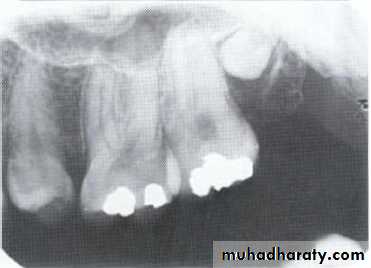

Hypodontia

Oligodontia

Anadontia

Developmental absence of all maxillary premolars and both mandibular second premolars. Note the retention of the maxillary primary canine as a result of the posterior position of the maxillary permanent canine.